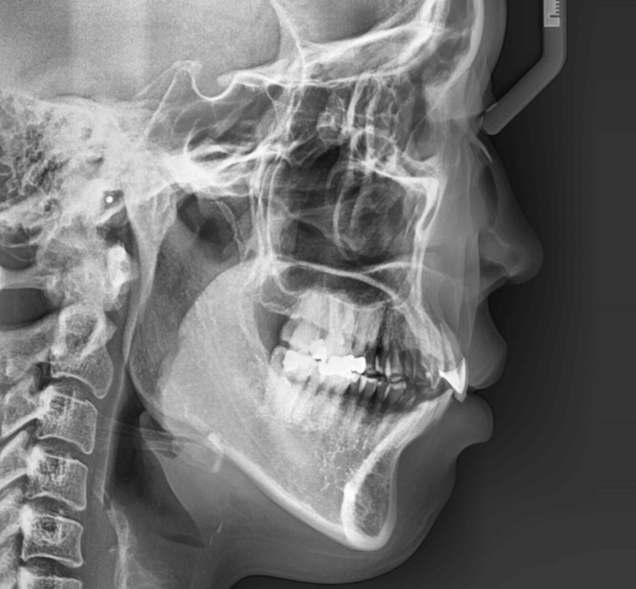

| 年齢・性別 | 34歳の女性 |

|---|---|

| 主訴 | 口元の突出感が気になり、将来的な咬合状態を整える目的で来院された患者様です。 |

| 治療期間・回数 | 3年3ヶ月・31回 |

| 費用 | 830,000円 |